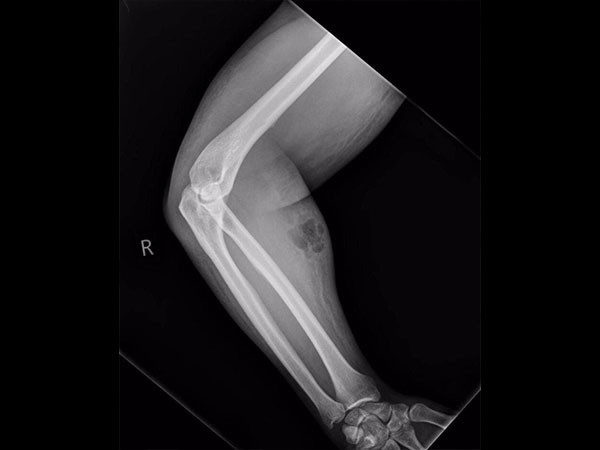

ವೈದ್ಯರು ಎಕ್ಸ್ ರೇ ತೆಗೆದರು

ವೈದ್ಯರು ಇದನ್ನು ನೋಡಿದ ಬಳಿಕ ಎಕ್ಸ್ ರೇ ಮಾಡಿಸಲು ಸೂಚಿಸಿದರು. ವೀರ್ಯವು ತುಂಬಾ ಮೃಧು ಅಂಗಾಂಶಗಳಿಗೆ ಸೋರಿಕೆಯಾದ ಪರಿಣಾಮ ಸೋಂಕು ಉಂಟಾಗಿತ್ತು. ತಿಂಗಳಿಗೊಮ್ಮೆ ಆತ ತನ್ನದೇ ವೀರ್ಯದ ಇಂಜೆಕ್ಷನ್ ತೆಗೆದುಕೊಳ್ಳುತ್ತಿದ್ದ ಕಾರಣದಿಂದ ವೀರ್ಯವು ಸೂಕ್ಷ್ಮ ಅಂಗಾಂಶಗಳಿಗೆ ತಲುಪಿ, ಅದರಿಂದ ಸೋಂಕು ಕಾಣಿಸಿಕೊಂಡಿತ್ತು. ಇದರ ಪರಿಣಾಮವಾಗಿ ಚರ್ಮದ ಸೋಂಕು ಸೆಲ್ಯುಲೈಟಿಸ್ ಕಾಣಿಸಿಕೊಂಡಿತ್ತು.

ವೈದ್ಯರು ಎಕ್ಸ್ ರೇ ತೆಗೆದ ಬಳಿಕ ಚಿಕಿತ್ಸೆಗೆ ಮುಂದಾಗುತ್ತಿದ್ದರೆ, ತಾನು ಚುಚ್ಚಿಕೊಂಡಿರುವಂತಹ ವೀರ್ಯವನ್ನು ವೈದ್ಯರಿಗೆ ತೆಗೆಯಲು ಆತ ಅವಕಾಶ ನೀಡಲಿಲ್ಲ.